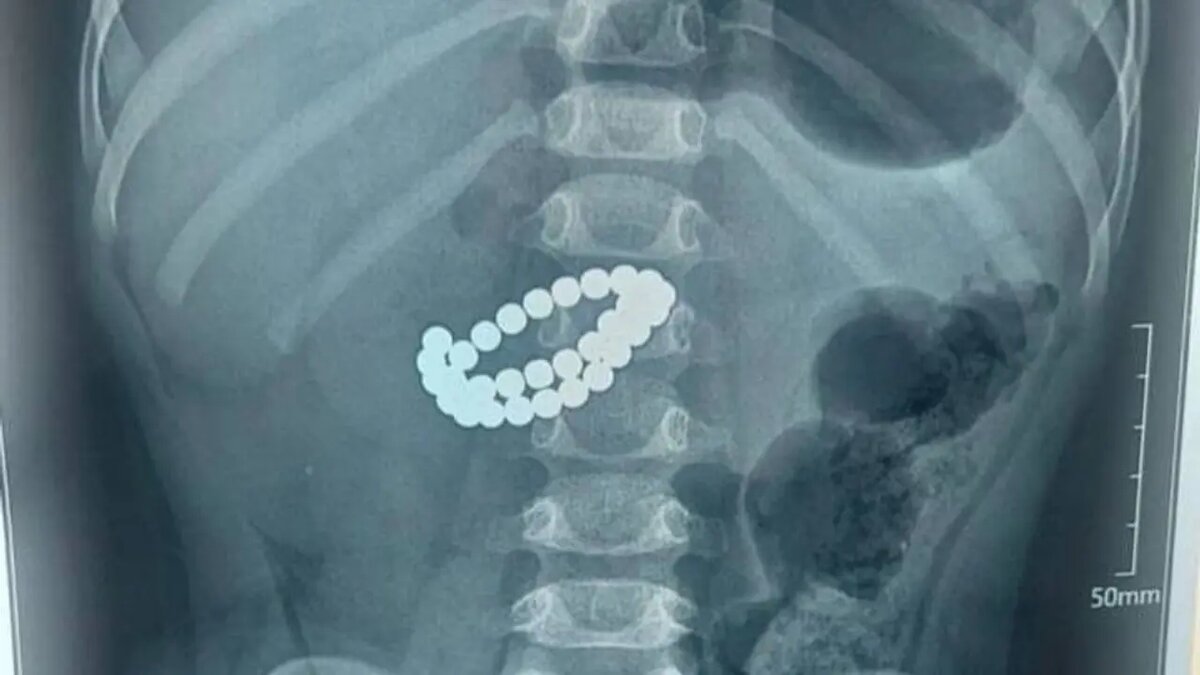

Ребенок проглотил 31 магнит: Срочная операция проведена

В Казахстане ребенок в возрасте одного года и девяти месяцев оказался в серьезной опасности после того, как проглотил 31 магнит. Об этом сообщает Zamin.uz.

По информации информационного агентства "Казинформ", ребенок был доставлен в тяжелом состоянии в больницу города Алматы. В ходе обследования было обнаружено множество магнитов в кишечнике.

Врачи отметили, что в нескольких местах кишечника ребенка образовались перфорации, а воспаление в брюшной полости усиливается. В данной ситуации время было крайне важным, и было принято решение немедленно провести экстренную операцию.

Хирурги открыли брюшную полость методом лапаротомии, удалили магниты, зашили поврежденные участки, очистили брюшную полость и установили дренаж. По словам врачей, магниты притягиваются друг к другу внутри кишечника, сжимая его стенки.

Это приводит к нарушению кровообращения, повреждению тканей и образованию отверстий в кишечнике. В результате в короткие сроки может развиться перитонит.